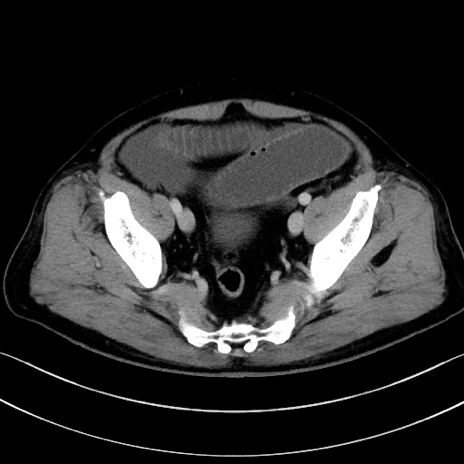

症例15(横断像)

【症例】70歳代男性

【主訴】腹痛

【現病歴】今朝から腹痛あり。全体的に痛い。特に左上の方。排ガスが今日はない。冷や汗が出る。

【既往歴】直腸癌術後

【身体所見】左側腹部〜上腹部に圧痛あり。腹膜刺激症状明らかなではない。軽度反跳痛。左下腹部に術後瘢痕あり。

【データ】WBC 7700、CRP 0.02